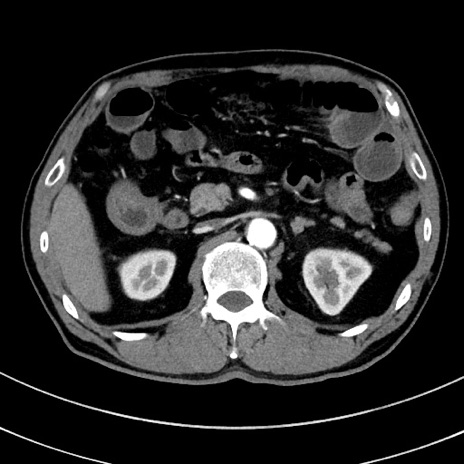

症例8(横断像)

【症例】 60歳代男性

【主訴】 黒色吐物

【現病歴】 4日前から嘔気自覚、2日前の朝食後にも嘔気あり、自分で手で嘔吐反射起こし嘔吐したところ血が混ざっていたため受診。

【既往歴】 5年前汎発性腹膜炎を伴う急性虫垂炎で手術、高血圧、前立腺肥大症、高脂血症

【身体所見】 腹部正中に手術癩痕あり 腹部平坦・軟圧痛なし膨満感あり

【データ】WBC 8400、CRP 4.54